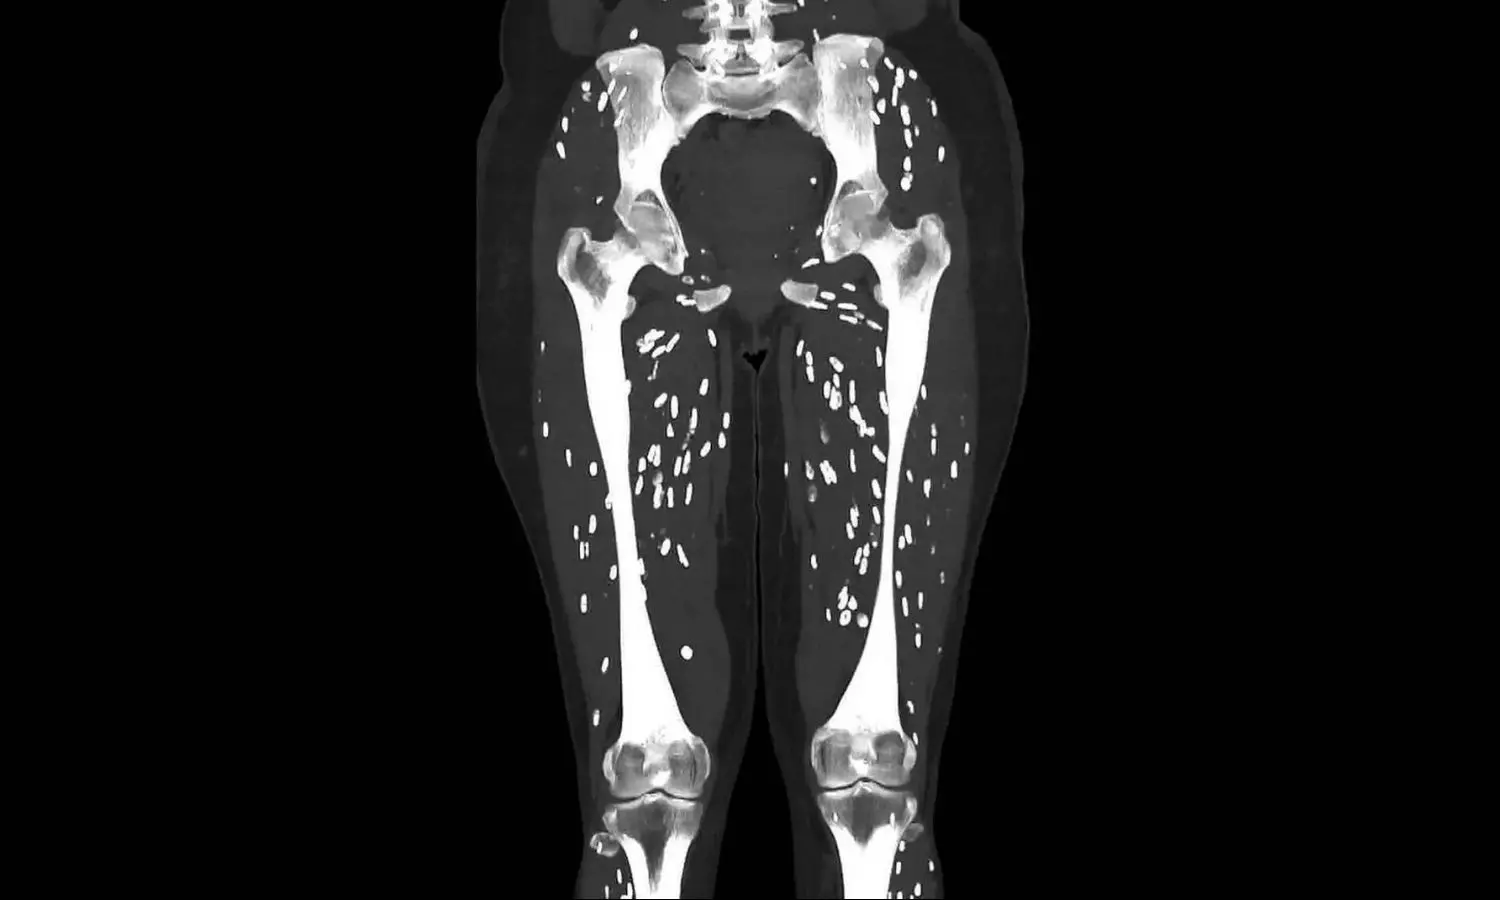

A CT scan of a person suffering from a parasitic infection caused by Pork Tapeworm was shared by a Us-based doctor on X.

Dr Sam Ghali, an emergency physician, shared the “craziest CT scan he has ever seen” on X. Doctor in his post mentions that the person is suffering from Cysticercosis which is a parasite infection caused by “ingestion of larval cysts of Taenia Solium, also known as: Pork Tapeworm.”

The image shows tiny rice-shaped particles around the bones in the lower body of the infected person.

Dr Sam further states that after the eggs are ingested they release larvae, penetrating the intestinal wall and invading into the blood and later spreading to anywhere in the body. The larvae’s common destinations are brain, eyes, subcutaneous tissues, and skeletal muscles and ultimately forms cysts.